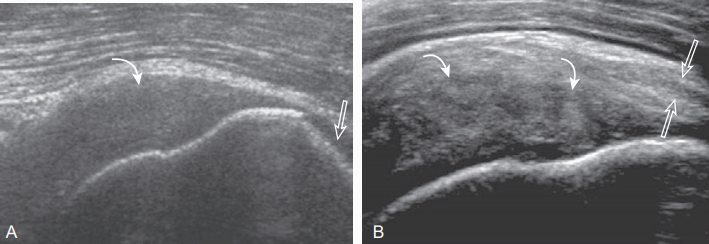

높은 에코의 가시위근힘줄이 찢어져서 경계가 좋은 낮은 에코 또는 에코 없는 부위가 관절 쪽에서 윤활주머니 쪽까지 연결되면, 전체증 째짐(full-thickness tear)이다. 앞쪽 먼 곳(원위부)에서 흔하고, 큰 거친 면 뼈겉질의 불규칙과 관련 있다. 힘줄 찢어진 곳에서 연골접촉면 징후가 보이면 째짐이 관절 쪽으로 연장되었음을 시사하는 간접소견이 된다. 전체증 째짐이 작을 때는 힘줄 두께의 감소가 없을 수 있다. 그렇지만 찢어짐이 커질수록 힘줄 두께가 줄어들고, 힘줄의 윗가장자리가 편평해지거나 오목해진다.

급성 째짐이 힘줄의 몸 쪽에서 생길 수 있는데 에코 없는 병변으로 흔히 보인다. 힘줄의 찢어진 정도(부분 또는 전체층 침범), 모양(긴축방향 또는 짧은 축방향), 크기, 다른 힘줄의 침범 여부를 판독내용에 포함하는 것이 중요하다. 힘줄의 광범위한 째짐에서는 힘줄의 가로와 세로 전체층이 찢어지고, 뒤 당김이 나타나는데 힘줄의 긴축방향영상에서 가장 잘 보인다.

힘줄의 만성 째짐에서는 큰 거친 면 뼈의 광범위한 재형성(extensive remodeling)이 있고, 힘줄끝이 가늘어지는데, 주변에 액체저류가 없을 수 있다. 그러나 같은 에코 또는 높은 에코를 보이는 윤활주머니염이 같이 있을 수 있다. 가시위근힘줄 째짐이 회전근 간격에서 뒤로 2.25cm 이상 연장되면 가시아래근힘줄을 침범한 소견이다. 가시위근힘줄째짐이 앞쪽으로 연장되면 어깨밑근의 윗가장자리를 침범할 수도 있다. 또한 근위축(muscle atrophy)을 보는 것도 중요한데, 이것은 수술 후 회전근띠의 기능 회복과 관련이 있다.

supraspinatus : full- thickness tear ( A:long axis B: short axis) 힘줄증